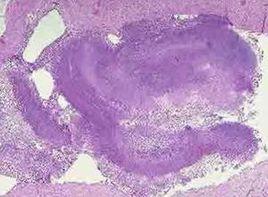

(2)厚壁空洞:洞壁厚度超過3mm.X線表現為形狀不規則的透光區,空洞周圍有密度增高的滲出性陰影。內壁往往凹凸不平或光滑整齊。見於肺膿腫、肺結核及肺癌。結核性空洞常無或僅有少量液面,而肺膿腫的空洞內多有明顯的液面,癌性空洞其內壁多不規則,有附壁結節。